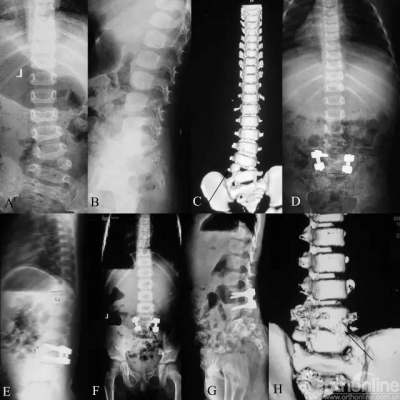

8岁患儿,先天性脊柱侧凸,侧凸弧累及胸段较长脊柱,呈进展性,畸形的发展将导致严重、僵硬的脊柱畸形,严重压迫心肺,影响患者生活质量甚至危及生命。而由于侧凸弧较长,早期的融合术会导致“短躯干”以及“胸廓发育不良综合征”。使用双生棒技术科在矫正畸形同时保留脊柱生长能力。患者术后2年随访,经历4次撑开术,矫形维持良好,心肺受压明显改善,脊柱纵向生长明显。

6岁男性先天性脊柱侧凸患儿。侧凸顶点存在巨大致畸生长力,单纯使用生长棒技术将面临反复出现内固定并发症的风险。为解决这个问题,我们首先对之进行顶椎的半椎体切除,仅在截骨水平的凸侧上下各植入一颗椎弓根螺钉;之后一期植入双棒生长棒。初次术后6个月进行收次撑开,至末次随访为止,该患儿共经历5次撑开。初次术后以及术后3年X线提示矫形良好;在脊柱生长的同时,矫形维持满意。胸廓发育良好。